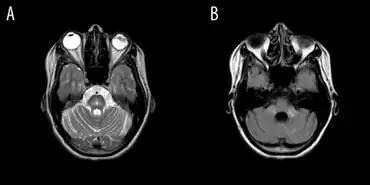

Olivopontocerebellar atrophy individual-a)Diffuse atrophy of cerebellum b) hyperintensity in bilateral middle cerebellar peduncles

MRI of the brain may show characteristics of OPCA, such as specific changes in the size of affected parts of the brain. This is more likely as the disease progresses; it is possible to have OPCA and have a normal brain MRI (especially within the first year of symptom onset).